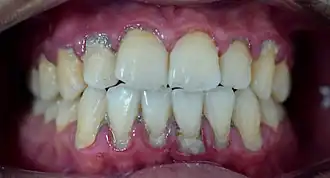

In dentistry, calculus or tartar is a form of hardened dental plaque. It is caused by precipitation of minerals from saliva and gingival crevicular fluid (GCF) in plaque on the teeth. This process of precipitation kills the bacterial cells within dental plaque, but the rough and hardened surface that is formed provides an ideal surface for further plaque formation. This leads to calculus buildup, which compromises the health of the gingiva (gums). Calculus can form both along the gumline, where it is referred to as supragingival ('above the gum'), and within the narrow sulcus that exists between the teeth and the gingiva, where it is referred to as subgingival ('below the gum').

Calculus formation is associated with a number of clinical manifestations, including bad breath, receding gums and chronically inflamed gingiva. Brushing and flossing can remove plaque from which calculus forms; however, once formed, calculus is too hard (firmly attached) to be removed with a toothbrush. Calculus buildup can be removed with ultrasonic tools or dental hand instruments (such as a periodontal scaler).

Plaque accumulation causes the gingiva to become irritated and inflamed, and this is referred to as gingivitis. When the gingiva become so irritated that there is a loss of the connective tissue fibers that attach the gums to the teeth and bone that surrounds the tooth, this is known as periodontitis. Dental plaque is not the sole cause of periodontitis; however it is many times referred to as a primary aetiology. Plaque that remains in the oral cavity long enough will eventually calcify and become calculus.[18] Calculus is detrimental to gingival health because it serves as a trap for increased plaque formation and retention; thus, calculus, along with other factors that cause a localized build-up of plaque, is referred to as a secondary aetiology of periodontitis.